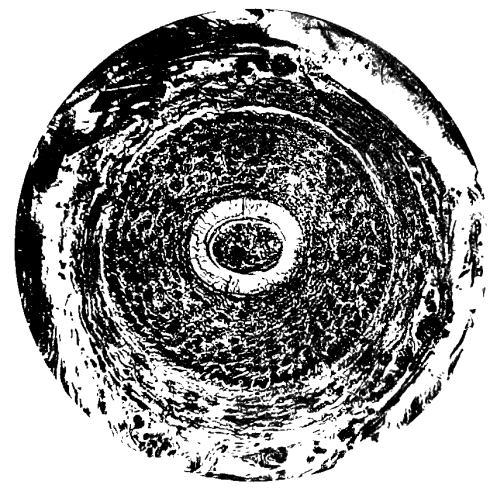

A plate, showing the centre of ossification in the lower epiphysis of the femur in a full time fœtus, has been introduced at the last moment, and will be found opposite page 64. References to the subject may also be found on pages 33 and 174.

Plate showing Centre of Ossification in the Lower Epiphysi of PAGE

Femur in full time Fœtus To face 64